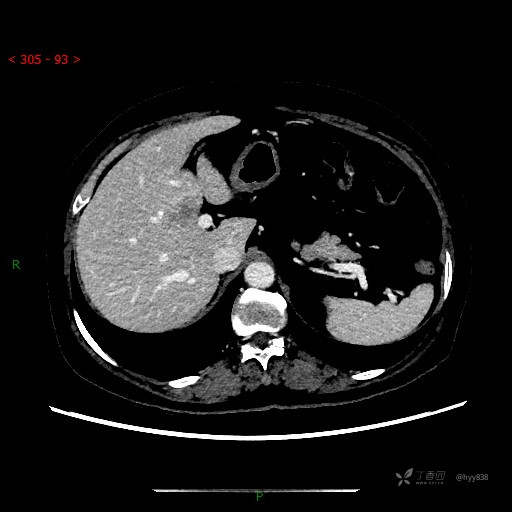

简要病史: 患者于一周前因胆囊结石于当地人民医院拟行手术治疗,后完善术前检查发现肝左内叶占位性病变,考虑肿瘤可能,患者无剑突下及右上腹疼痛不适,无明显反酸、嗳气,无畏寒、头晕、头痛,无尿频、尿急、尿痛等不适,今为求进一步治疗特来我院就诊,门诊以“肝占位”收住我科。 患者病程中精神、睡眠、饮食尚可,大小便正常、体力体重无明显变化

临床诊断:肝占位

讨论:病变性质?